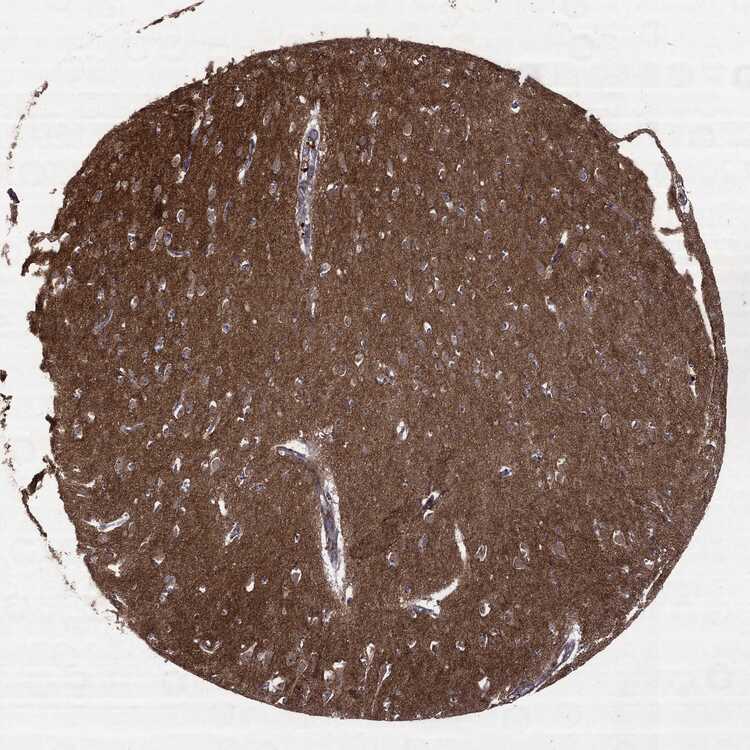

HIPPOCAMPUS - Antibody stainingi

Antibody staining in the annotated cell types in the current human tissue is reported as not detected, low, medium, or high, based on conventional immunohistochemistry profiling in selected tissues. This score is based on the combination of the staining intensity and fraction of stained cells.

Each image is clickable and will lead to virtual microscopy that enables deeper exploration of all samples and also displays staining intensity scores, fraction scores and subcellular localization as well as patient and tissue information for each sample.

Antibody HPA031335Antibody CAB004076Antibody CAB080153Antibody CAB080157

Glial cells Not detectedNot detectedNot detectedNot detected

Neuronal cells Not detectedLowMediumMedium